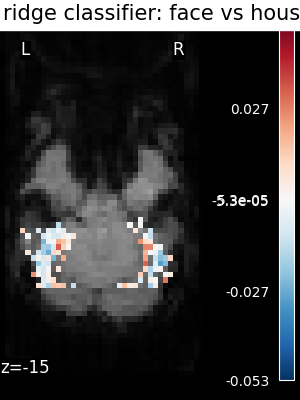

The corresponding weight maps (below) differ widely from one estimator to the other, although the prediction scores are fairly similar. In other terms, a well-performing estimator in terms of prediction error gives us little guarantee on the brain maps.

../_images/sphx_glr_plot_haxby_different_estimators_006.png ../_images/sphx_glr_plot_haxby_different_estimators_005.png ../_images/sphx_glr_plot_haxby_different_estimators_004.png ../_images/sphx_glr_plot_haxby_different_estimators_002.png ../_images/sphx_glr_plot_haxby_different_estimators_003.png